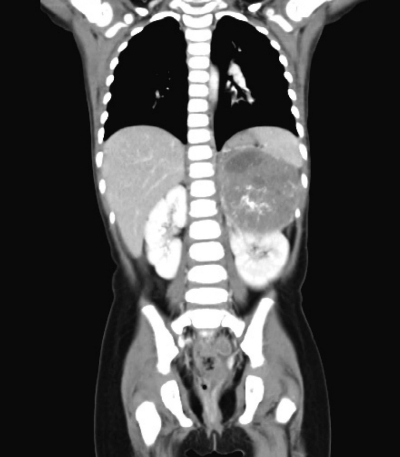

尿所見:蛋白(-)、糖(-)、潜血(-)、沈渣に白血球を認めない。血液所見:赤血球 428 万、Hb 11.1 g/dL、Ht 34 %、白血球 12,600、血小板 58 万。血液生化学所見:総蛋白 7.6 g/dL、総ビリルビン 0.2 mg/dL、AST 35 U/L、ALT9U/L、LD 589 U/L(基準 334〜742)、尿素窒素 7 mg/dL、クレアチニン 0.2 mg/dL、尿酸 2.7 mg/dL、Na 141 mEq/L、K3.9 mEq/L、Cl 104 mEq/L。免疫血清学所見:CRP 3.4 mg/dL、NSE 169 ng/mL(基準 10 以下)、α-フェトプロテイン(AFP)2.5 ng/mL(基準 10 以下)、尿中バニリルマンデル酸(VMA)96 μg/mgCr(基準 6〜11)。腹部単純CTと胸腹部造影CTとを示す。